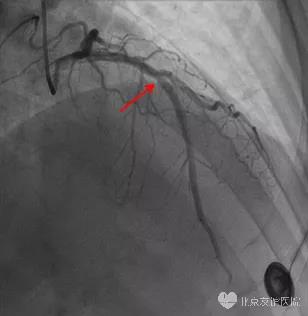

患者症状持续不缓解,行急诊冠脉造影检查,结果如图3:左前降支中段弥漫性狭窄100%完全闭塞,TIMI 0级,行PCI治疗后,LAD前向血流恢复至TIMI 3级,如图4;术后复查心电图,相应导联ST-T改变恢复正常,如图5。

图3:左前降支中段弥漫性狭窄100%完全闭塞,TIMI 0级

图4:LAD-PCI术后,LAD前向血流恢复至TIMI 3级